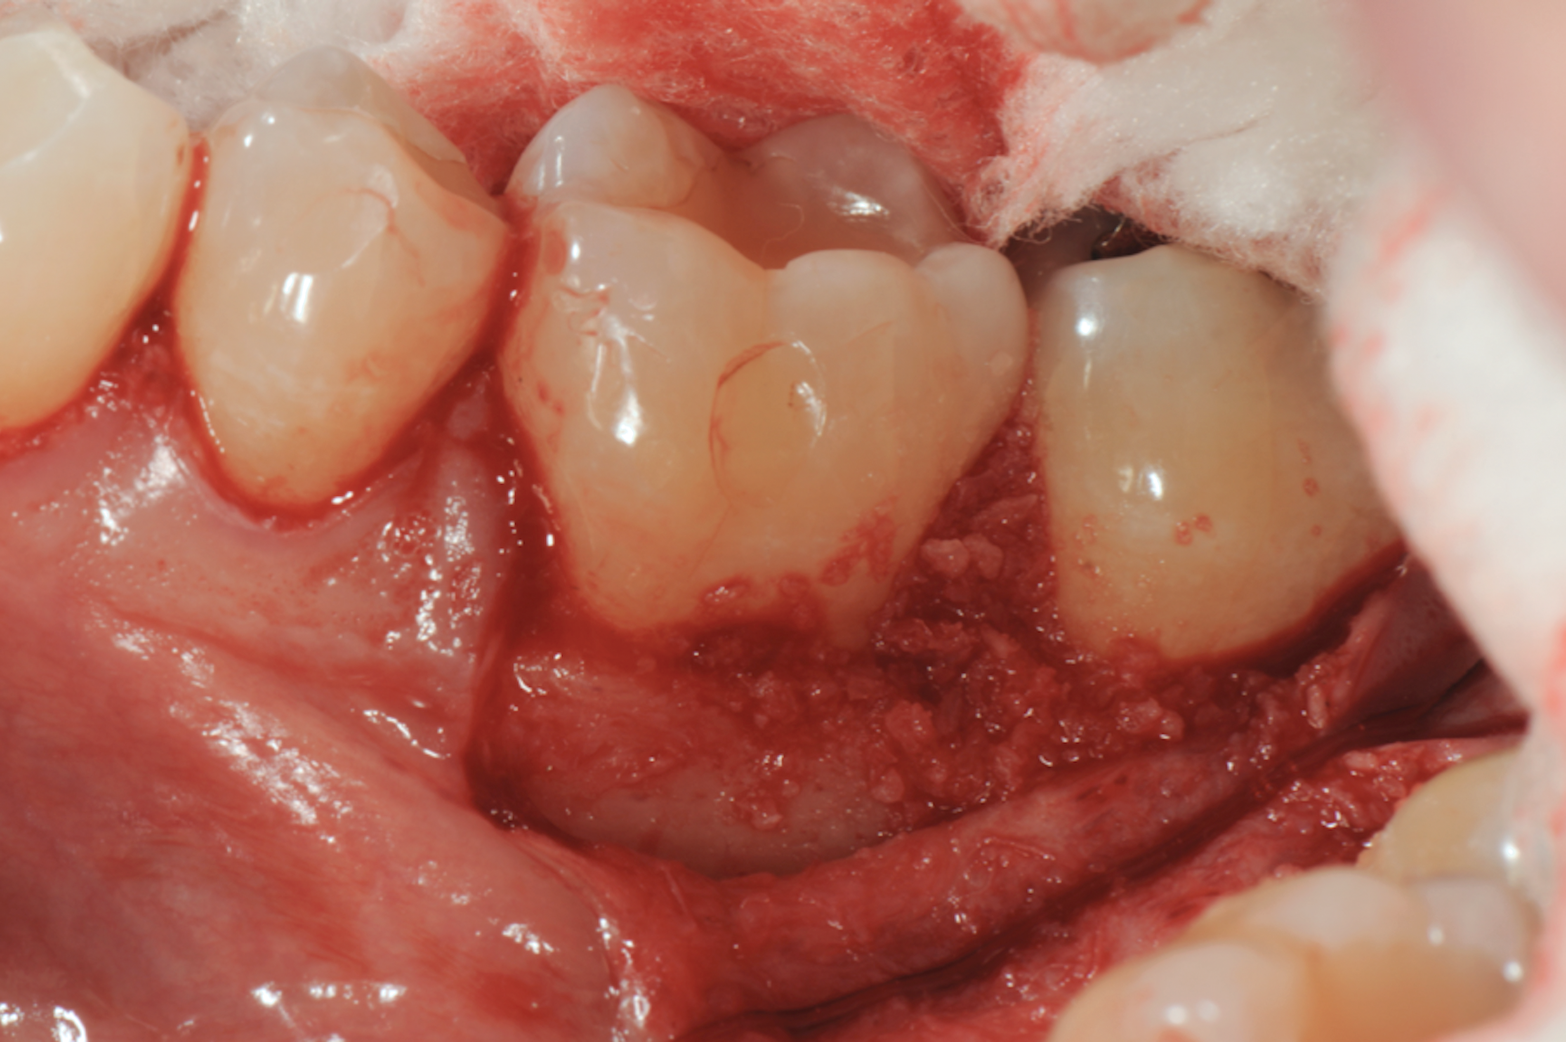

Fig 8. Combination therapy in which rhPDGF-BB was combined with FDBA (Fig 8) and packed into the bone defect (Fig 9).

Figure 8

Fig 9. Combination therapy in which rhPDGF-BB was combined with FDBA (Fig 8) and packed into the bone defect (Fig 9).

Figure 9

Fig 10. Combination therapy included the use of an amnion-chorion membrane, which was customized (Fig 10) and placed over the interproximal aspect of the bone defect (Fig 11).

v

Fig 11. Combination therapy included the use of an amnion-chorion membrane, which was customized (Fig 10) and placed over the interproximal aspect of the bone defect (Fig 11).

Figure 11